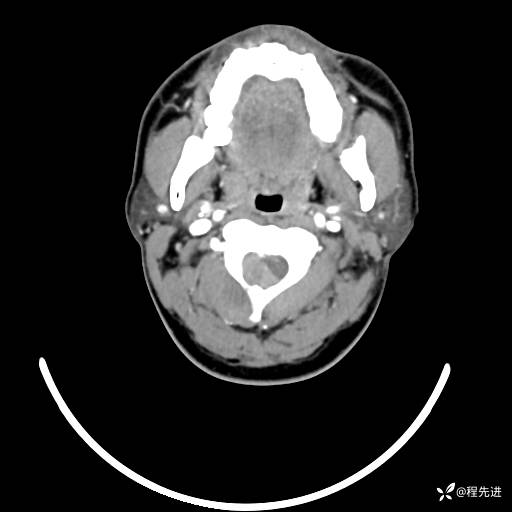

CT平扫+增强: